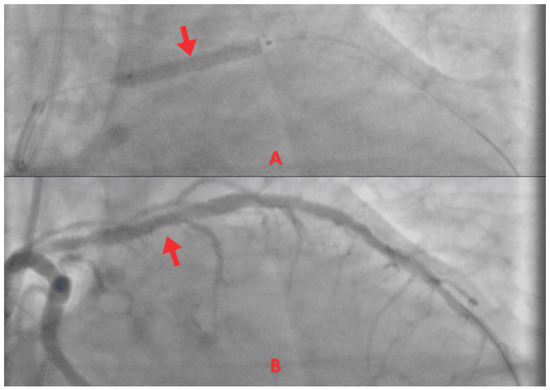

| 8 May | Mild retrosternal chest pain, absence of dyspnea, and improved ventilatory mechanics. | - | - | Coronary angiography: critical proximal LAD stenosis (>90%). Chronic atherosclerotic disease in the circumflex artery, without significant obstructive lesions. Percutaneous coronary intervention (PCI): angioplasty + drug-eluting stenting in the proximal LAD (TIMI 3 flow). |